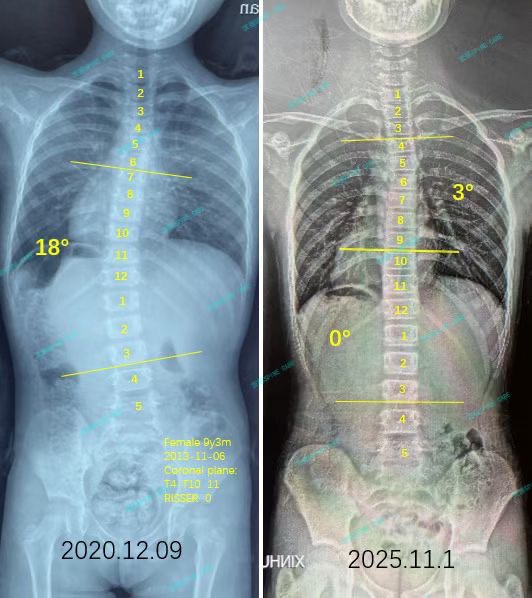

我是娴娴,左胸腰弯从18度到0度,我会继续维持的!

案例主人:娴娴 发现侧弯年龄:7岁 侧弯情况Cobb角测18°

最近的拍片结果显示我的侧弯又好转了一些,现在已经0度啦~为了感谢衷德团队的帮助与陪伴,我送给他们一幅画,谢谢你们让我保持健康~

The recent x-ray results show that my scoliosis has improved a little more, and now it is already 0 degree ~ To thank Zhongde's team for their help and company, I drew them a painting. Thank you for keeping me healthy ~